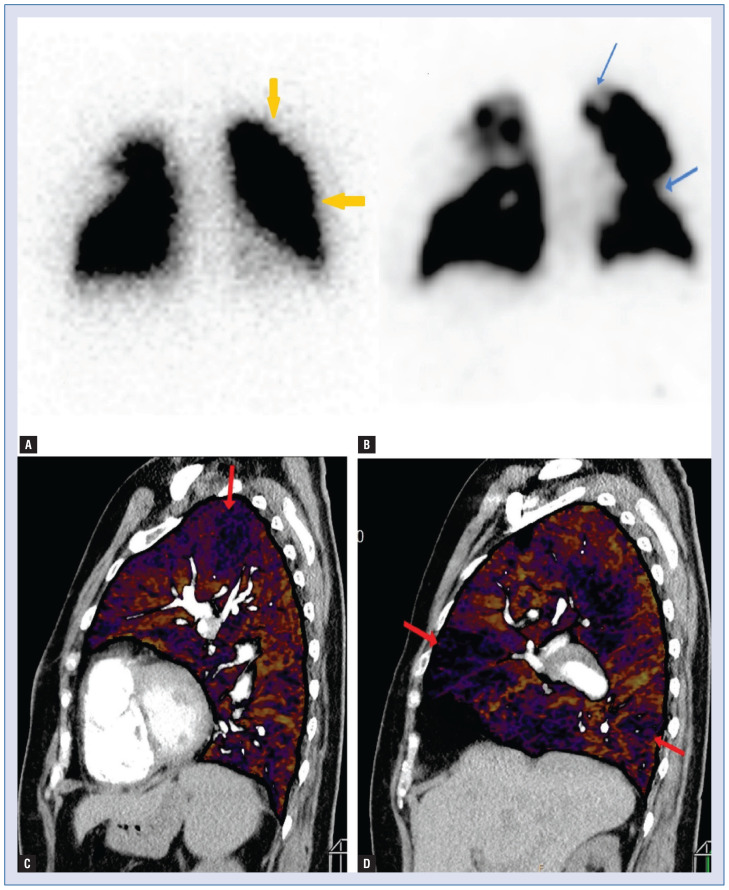

Abstract Image